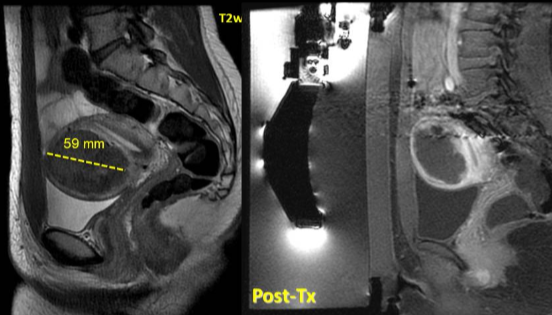

28 岁女性,下腹部疼痛及腹部紧张症状

![]() |

| 治疗前后对比 |

随访

| 6个月和12个月随访 |

44岁,患有盆腔疼痛和阴道出血症状